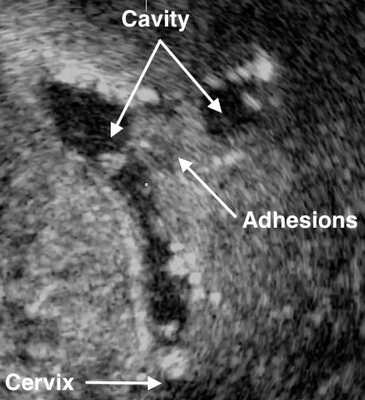

УЗИ малого таза при синдроме Ашермана малоинформативно; эхоскопическая картина может быть представлена нерегулярными конурами эндометрия, в случае гематометры - анэхогенным образованием в полости матки. Проведении гистеросальпингоскопии позволяет более четко определять наличие внутриматочных сращений.

Наиболее полная картина представляется при выполнении гистеросальпингографии и гистероскопии. Гистеросальпингография выявляет одиночные либо множественные дефекты наполнения, имеющие лакунообразную форму и различные размеры. При плотных множественных внутриматочных синехиях полость матки на рентгенограмме выглядит многокамерной, с мелкими, соединяющими отдельные камеры протоками. Однако нередко гистеросальпингография сопровождается ложноположительными результатами из-за наличия в матке слизи, искривлений, обрывков эндометрия. При эндоскопической гистероскопии внутриматочные синехии определяются как белесоватые бессосудистые тяжи разной плотности и длины, соединяющие стенки матки, обнаруживается облитерация или деформация полости матки.